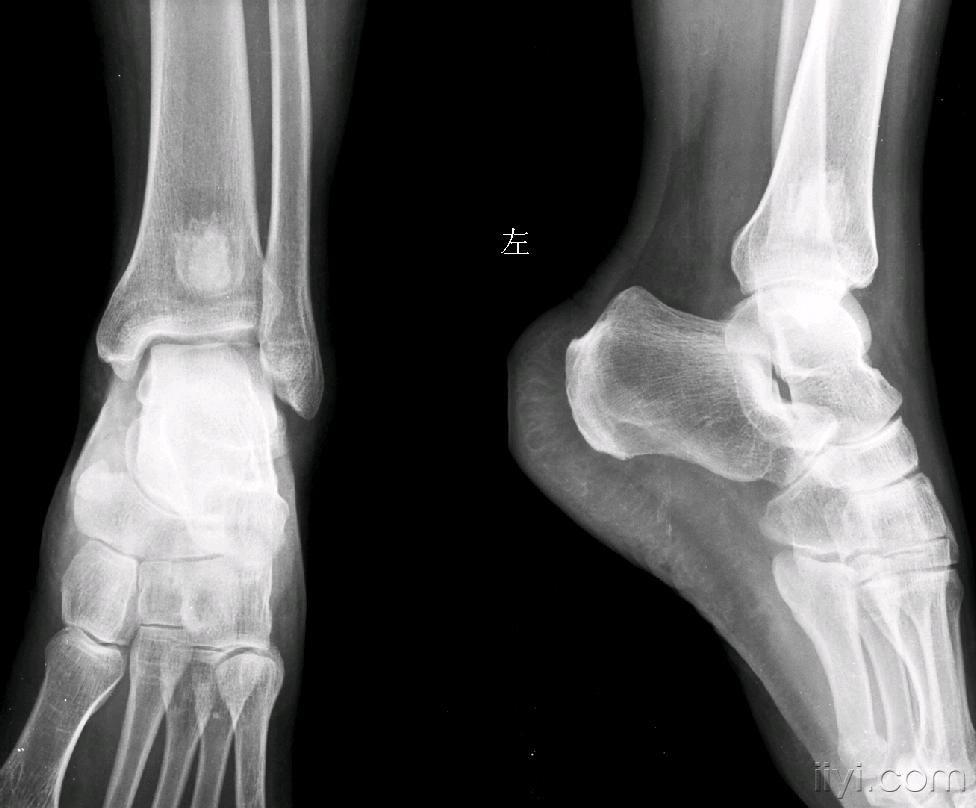

胫端下端骨质异常大家讨论骨梗死

图片尺寸976x808